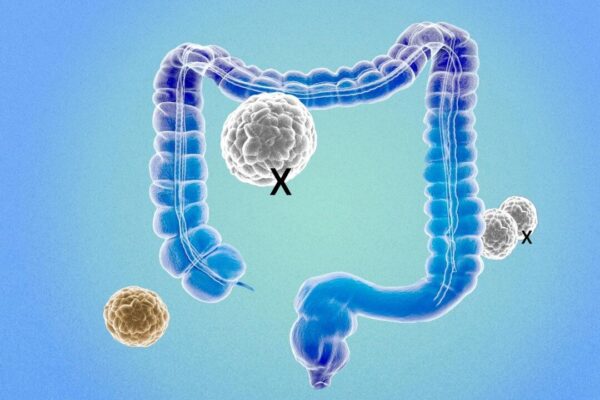

効果1 抗がん作用

カリフラワーとブロッコリーに豊富に含まれているスルフォラファン(Sulforaphane)は抗がん作用が認められています。2023年に行ったブロッコリーに関する研究では、「スルフォラファン」が乳がん、前立腺がん、肺がん、大腸がんなどさまざまな癌細胞の成長を抑制でき、細胞のアポトーシス(自主的な死)を誘導する機能があることが示されています。